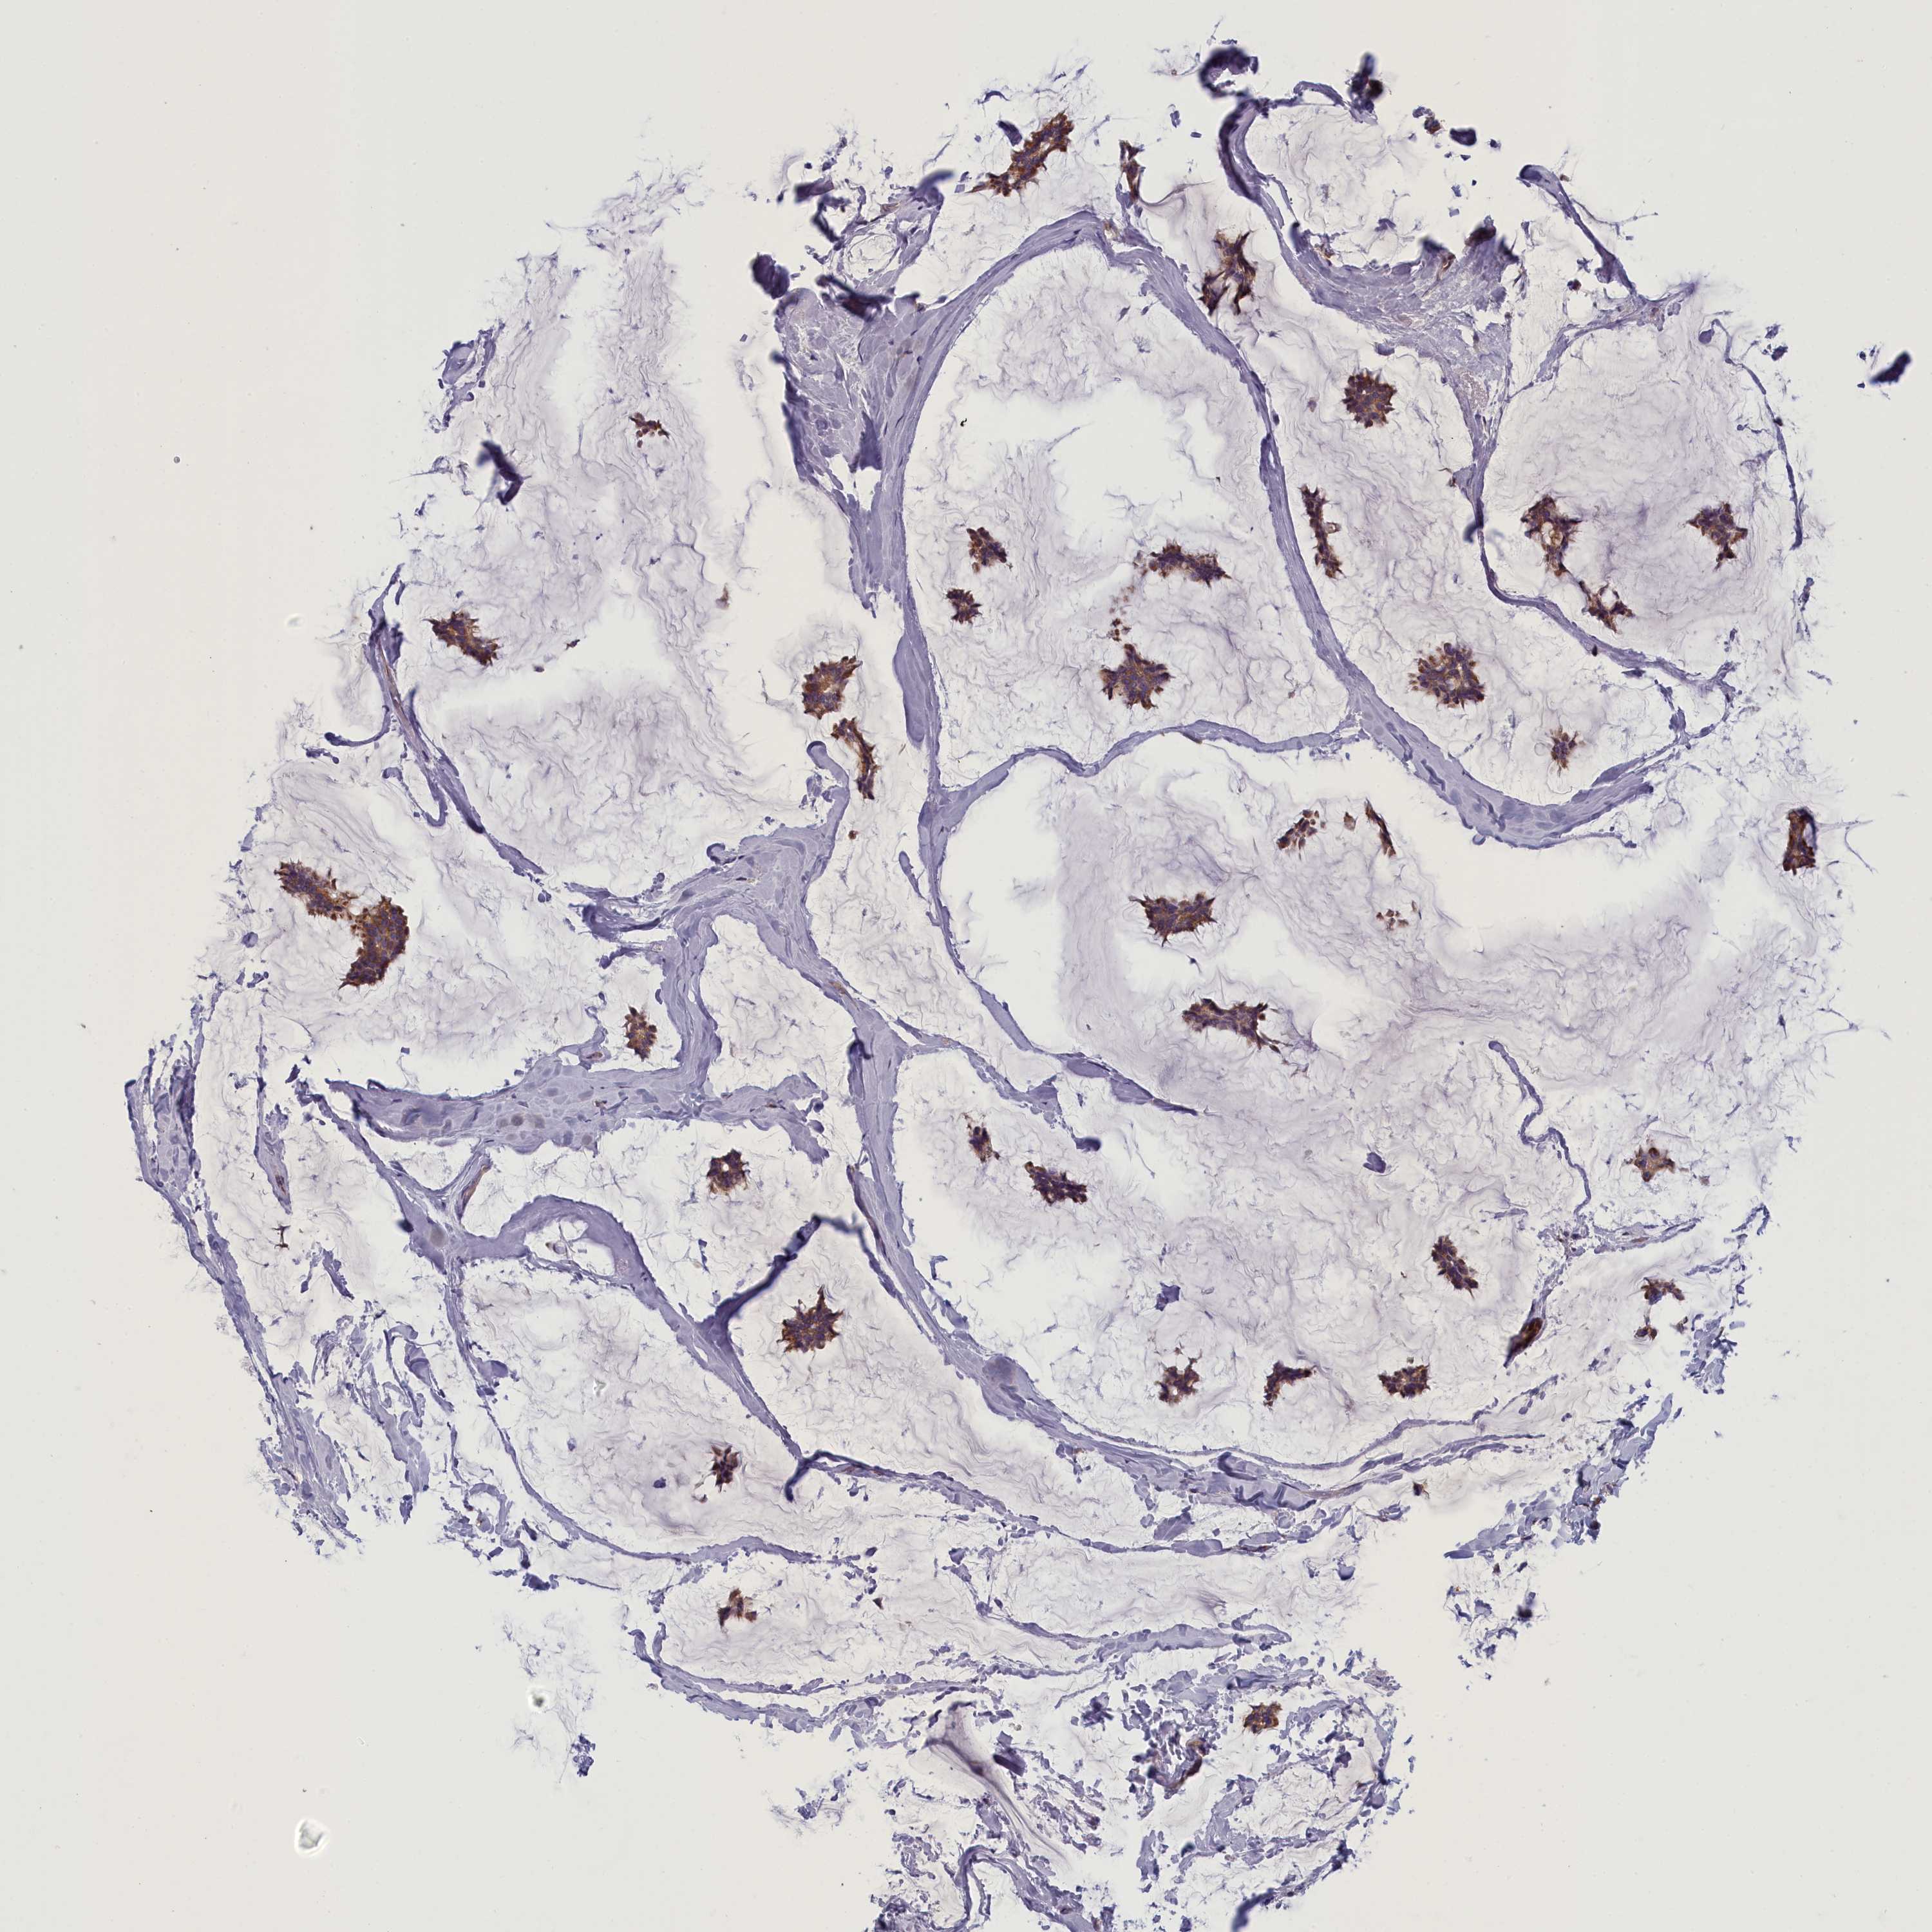

CANCER BREAST CANCER Show tissue menu

BRCA TCGA BRCA VALIDATION PROTEIN EXPRESSION

ANTIBODIES

AND

VALIDATION